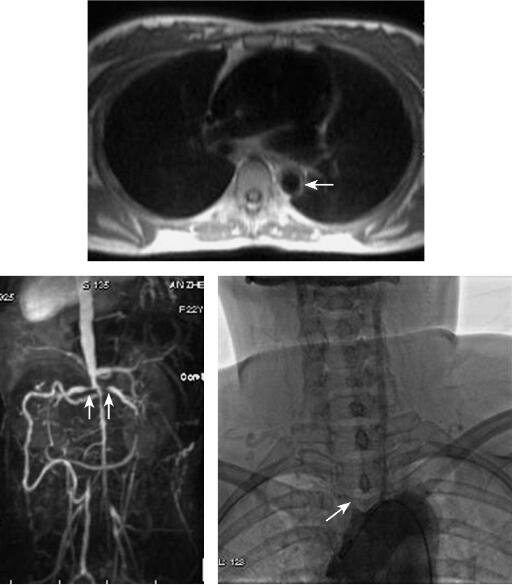

磁共振成像检查:应用1.5T高场强MRI仪(Magnetom Sonata,Siemens),16通道体部表面线圈,患者取仰卧位,头先进,黑血、true-FISP脉冲序列获得体轴横断、斜矢状位平扫,然后再行主动脉CE-MRA扫描,应用钆喷酸葡胺对比剂,按0.2mmol/kg体重剂量、流率为3.5ml/s经静脉注射对比剂。心脏MRI检查方案见表1。影像学检查见图1。

图1 大动脉炎

MRI表现:MR黑血序列可见胸主动脉管壁增厚,管壁不规则。MRA:胸主动脉中远段管壁不规则,腹主动脉下段管腔闭塞,腹腔干、肠系膜上动脉、双肾动脉开口处管腔重度狭窄。

头颈部DSA:头臂血管仅见出左颈总动脉,且近段部重度狭窄,右颈总动脉起始部鼠尾样狭窄闭塞;左锁骨下动脉闭塞,未见显影。

大动脉炎的MRI特点:受累血管管壁环形增厚,急性期T2WI显示病变为高信号。CEMRA显示主动脉以及一级分支开口部重度狭窄,多呈对称性狭窄。